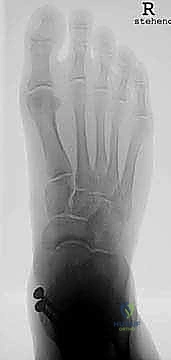

* التصوير الشعاعي المتقدم: صور أشعة سينية (X-rays) في وضعية الوقوف (تحميل الوزن) لتقييم المحور الميكانيكي للساق والقدم.

* تقييم التوازن: التأكد من عدم وجود تشوهات في القدم (مثل القدم المسطحة الشديدة أو التقوس) التي قد تؤثر على عمر المفصل الصناعي. إذا وجدت هذه التشوهات، قد يقرر الدكتور هطيف إصلاحها جراحياً في نفس الوقت لضمان بيئة ميكانيكية مثالية للمفصل الجديد.